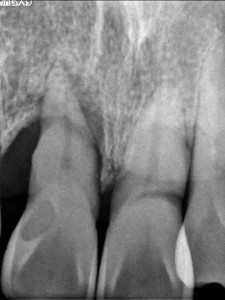

歯周病で溶けた骨

歯周病はサイレントキラーとも呼ばれ、本人が気付かないまま、歯ぐきの中の骨を溶かしていってしまいます。

末期になってはじめて痛みや腫れ、歯の揺れといった症状が起こることが多いので、非常に恐ろしい病気と言えます。

健康な骨であれば、歯を十分に支えることができるため、揺れて抜け落ちてしまうこともありません。しかし歯周病が進んでいくと、歯の周りの骨が溶けて歯を支えることができなくなってしまうため、歯が揺れてきて、ついには抜け落ちてしまいます。

歯ぐきの中に歯石が付着し、周りの骨が溶けています

さらに歯周病が進んでくると歯ぐきの中にも歯石や汚れがたまってきます。

歯石や汚れは「歯周病菌の基地」のようなものなので、歯ぐきの中に歯石があると歯周病菌による歯を支える骨が直接攻撃されてしまい、比較的早く骨が溶けていってしまいます。